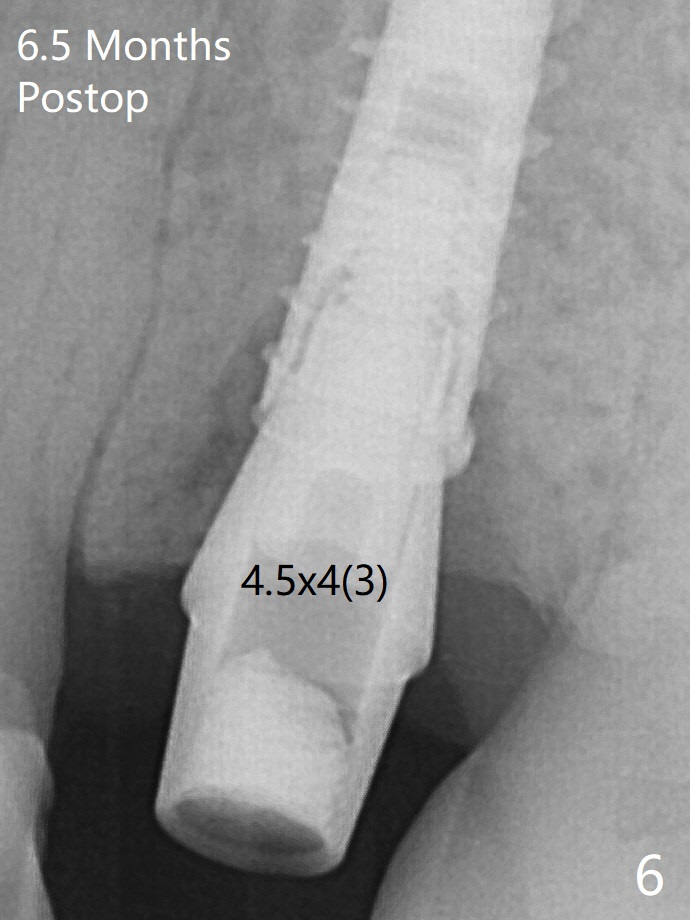

A 4x13 mm IBS implant is seated incompletely.  The osteotomy is further enlarged by 3.8 mm Magic Drill for 11 mm and deepened with 3 mm drill until 18 mm.  Finally the implant is placed at a satisfactory level with insertion torque > 50 Ncm (Fig.5).  The patient chooses to return for impression 6 months postop (Fig.6).  The abutment changes to a 4x4(4) mm one.  The crown is recemented  nearly 2 years post cementation, which is related to distal and deep placement of the implant and bruxism (Fig.7).